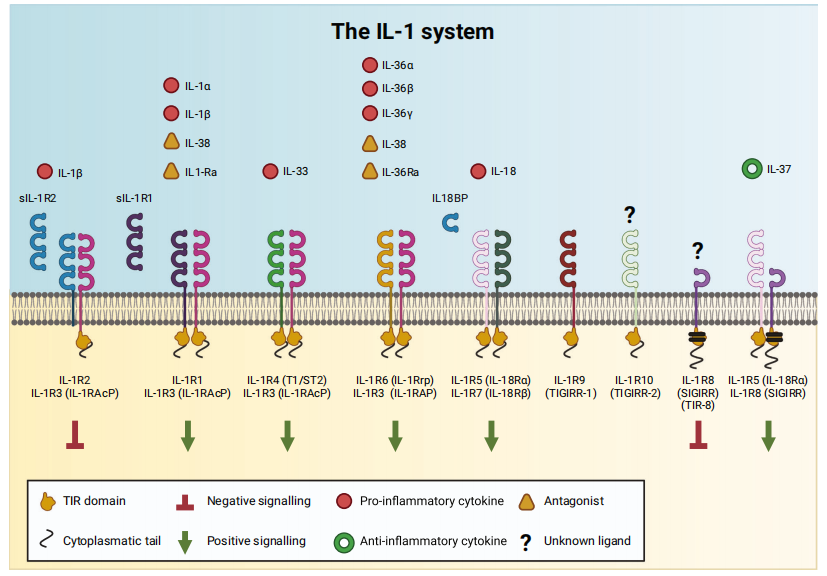

一、IL-1的“双面人生”:炎症的启动器与免疫的调控者白介素-1(Interleukin-1, IL-1)并非一个单一的分子,而是一个庞大的家族,其中最核心的成员是

IL-1α和

IL-1β。这两种细胞因子是机体抵御病原体入侵和组织损伤的“急先锋”,它们在炎症和免疫反应中扮演着至关重要的角色,堪称免疫系统的“总指挥”之一。

2. IL-1的核心生物学功能IL-1的生物活性极为广泛,作用于全身多种组织和器官,它主要通过结合细胞表面的I型IL-1受体(IL-1R1)来启动信号转导。

1. IL-1的信号转导机制当IL-1α或IL-1β与细胞表面的I型IL-1受体(IL-1R1)结合时,并非孤军奋战。它需要一个“帮手”——

IL-1受体辅助蛋白(IL-1RAcP),三者形成异源三聚体复合物。这个复合物的细胞内部分包含一个共同的结构域:

Toll样/IL-1R(TIR)结构域。

- 阿那白滞素(Anakinra): 一种重组的IL-1受体拮抗剂(IL-1Ra)。IL-1Ra是人体内天然存在的IL-1抑制剂,它可以结合到IL-1R1上,但不会激活下游信号。阿那白滞素模仿这种天然机制,竞争性地阻断IL-1α和IL-1β的作用。它已获批用于治疗类风湿性关节炎、幼年特发性关节炎和CAPS等。

- 利洛西普(Rilonacept): 一种由IL-1受体的细胞外域组成的融合蛋白,作为一个“诱饵受体”(Decoy Receptor),像海绵一样吸附IL-1α和IL-1β,阻止它们到达真正的细胞受体。主要用于治疗CAPS。